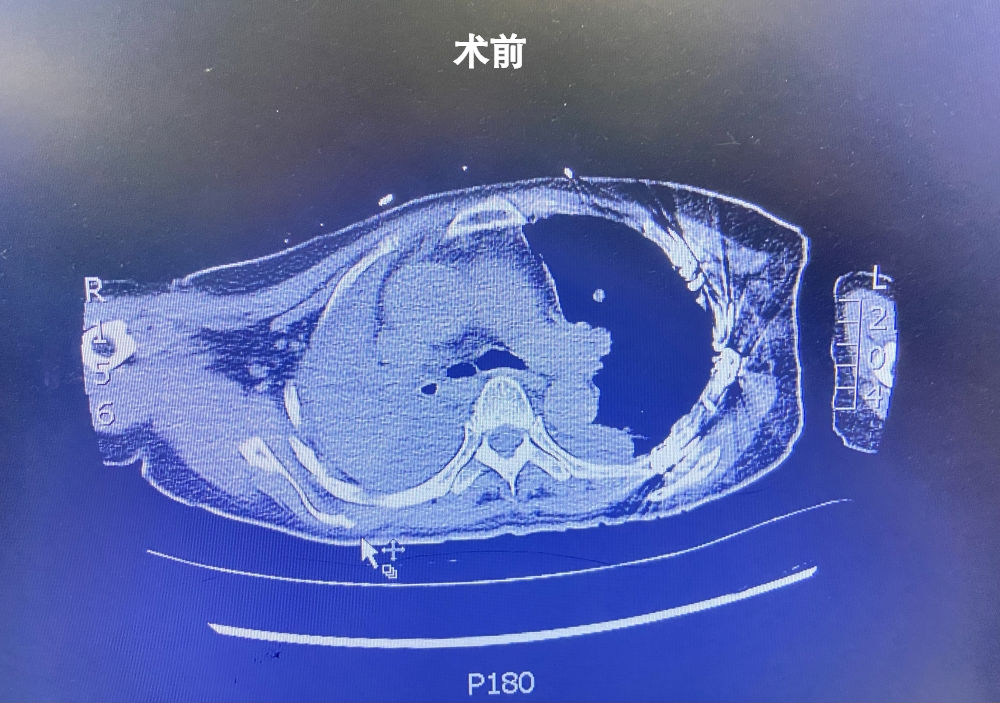

该患者为55岁女性,因“车祸致多发肋骨骨折、血气胸、肩胛骨骨折,在当地区医院行肋骨骨折切开复位内固定术后1+月,无明显诱因突发呼吸困难并加重5天,予以气管插管呼吸机辅助呼吸未缓解”转入我院。我院急诊CT显示:

1.右肺密度增高,右主支气管及下叶支气管内密度增高,右肺上叶及中叶支气管未见显示,纵隔右移,考虑右主支气管及其分支痰栓并右肺不张?右侧胸腔积液积血。

2.左侧胸腔少量积液积血伴左肺后份部分膨胀不全。

3.心脏增大,心包积液,肺动脉干增粗。血气提示氧合指数进行性下降。入院诊断:右侧支气管断裂伴肺不张,双侧胸腔血胸;I型呼吸衰竭;心脏增大;肺动脉干增粗;胸4椎体压缩性骨折......